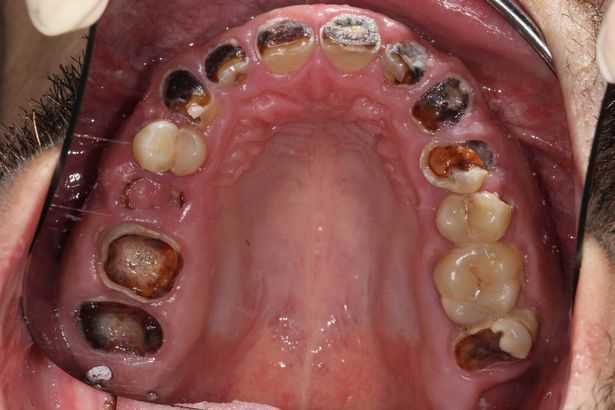

32-річний Майкл Шерідан випивав шість літрів солодкої газованої води в день і через це позбувся практично всіх зубів.

Як повідомляє The Sun, йому довелося видалити 27 знилих повністю зубів і замінити їх протезами.

Останнім часом чоловікові доводилося їсти тільки рідку їжу, бо його турбував постійний зубний біль.